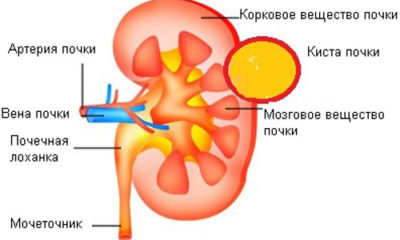

Кіста нирки - це доброякісна пухлина в органі, яка є капсулою, наповненою рідиною. Не можна плутати нирковий освіту з кістою при генетичне захворювання (полікістоз). Вони відрізняються характером перебігу і різною будовою пухлини. Сьогодні до кінця невідомі причина освіти. Це саме захворювання лідирує серед всіх ниркових.

Кіста - це порушення в структурному ладі органу, представлене у вигляді порожнини (порожнечі), заповненої рідиною жовтого кольору.

Існує два варіанти будови - простий і складний. Солітарні (просте) освіту в нирках має форму одиничної порожнини, в той час як складне визначається декількома відсіками. Саме через велику кількість частин багатоскладних кісту важче лікувати. Просте освіту набагато безпечніше, ніж складне, воно майже не дає ускладнень.

За місцем освіти кіста розділяється на підгрупи:

- Парапельвікальная (характерне утворення в нирковій мисці, вважається, що ця різновиди зростає з лімфатичних судин).

- Паренхіматозна - розвивається на паренхімі органу.